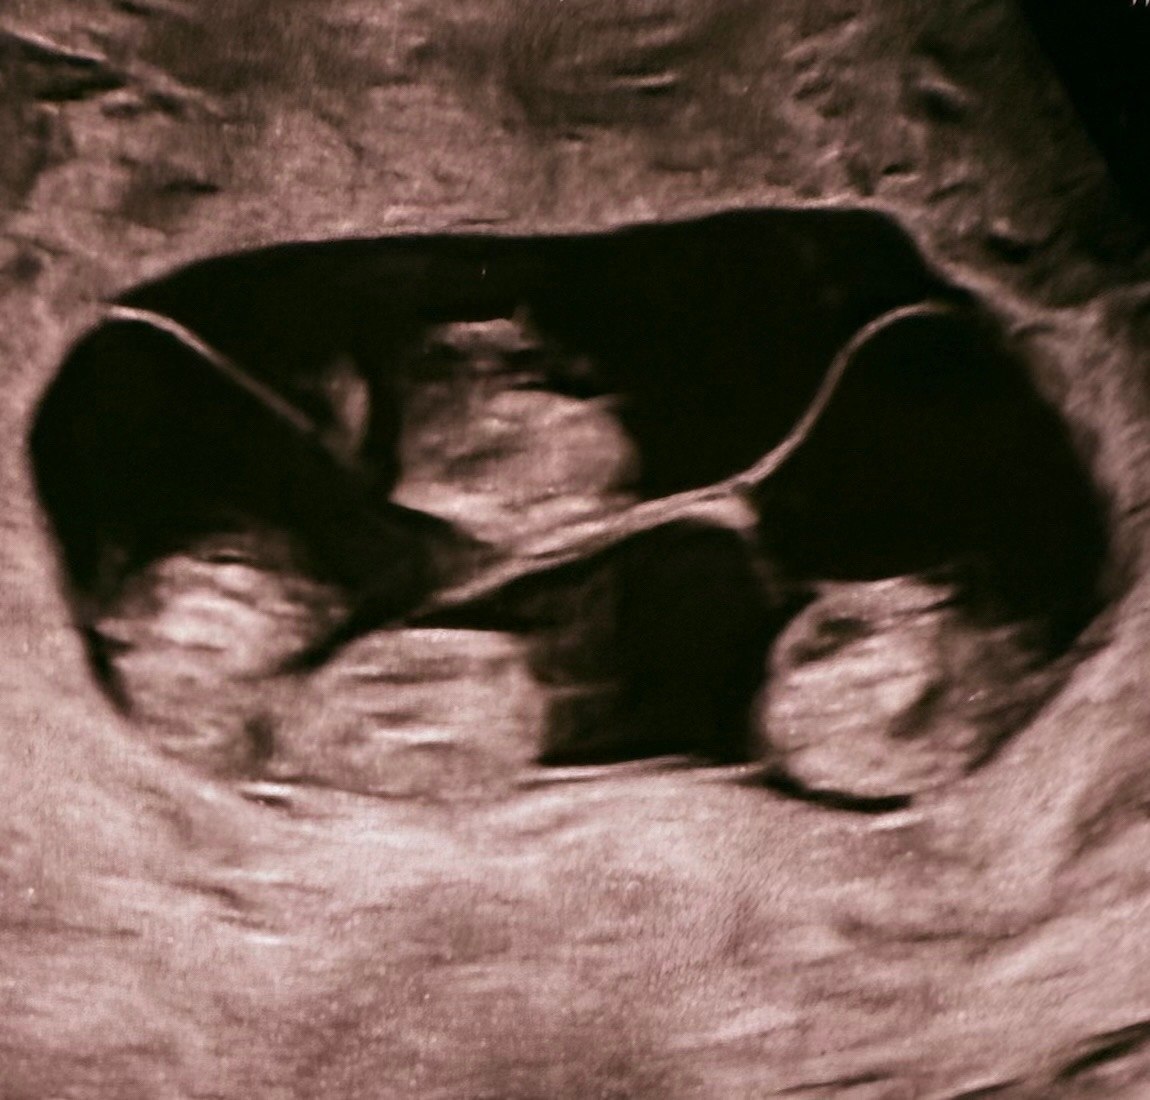

В Петербурге женщина родила сразу четырех девочек, причем все они — однояйцевые близнецы

Между прочим, это первый в России случай однояйцевой четверни. Вероятность таких родов один на 15,5 млн. Радостной новостью поделился один из профессоров, который курировал беременность россиянки.

Малышки родились недоношенными посредством кесарева сечения на 32 неделе. Вес девочек составил 1400, 1570, 1640 и 1360 граммов, рост — 38, 41, 41 и 37 см соответственно. Для такого раннего срока показатели считаются хорошими.